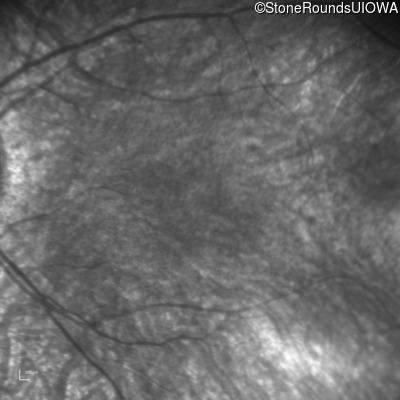

Infrared Fundus Photograph - Left - 20/80

Exemplar